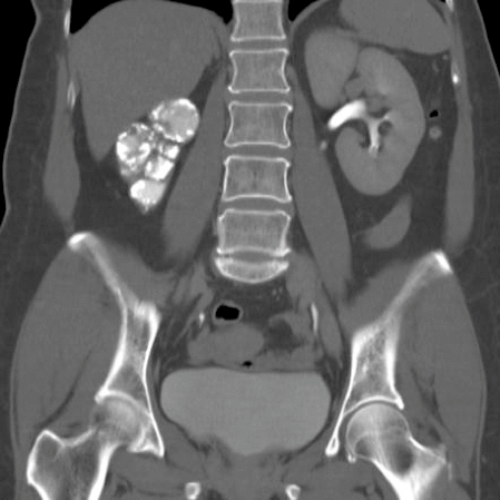

Below is a selection of radiological images of the urinary tract.

Figure 1.

- What do the two clinical images represent in Figure 1?

- What are the possible causes?

- Figure 2 shows other radiological features of one of these possible causes. What is the likely diagnosis? How often does this condition affect the urinary tract?

Case 2

-

Papillary necrosis.

POSTCARDS: Pyelonephritis, Obstruction, Sickle cell disease, TB, Cirrhosis, Analgesia abuse, Renal vein thrombosis, Diabetes, Systemic vasculitis.

TB, 15% genitourinary tract involvement. A: left autonephrectomy, B: non-functioning right kidney with left sided infundibular scarring and caliectasis, left distal ureteric stricture, small capacity bladder.